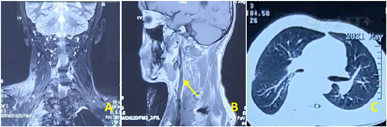

影像学检查:CT平扫+增强:右颈部胸锁乳突肌内侧肌间隙内肿瘤性病变,大小约166 mm×85 mm,考虑神经纤维瘤可能;由右锁骨下动脉及右侧椎动脉供血,右颈总动脉、气管及临近结构向左移位。右锁骨下动脉及颈内静脉被肿瘤紧密包绕(图2)。MR平扫+增强显示:肿物与C6-T2右侧椎间孔关系密切,考虑神经纤维瘤可能,右锁骨下动脉及右侧椎动脉供血。我们通过提取术前薄层CT增强数据,通过Mimics V20.0(比利时Materialise公司)软件重建患者肿瘤及邻近组织的三维立体图像,从而更直观观察肿瘤大小、形态以及规划手术切除方案(图3)。

同大多数软组织肿瘤一样,巨大神经纤维瘤切除时所出现的大出血往往导致死亡率升高[10]。因此,有效的阻止和遏制失血性休克的发生及发展是至关重要的。显然,异体血输注及术中自体血回输仍然是防止失血性休克的有效手段之一[11]。另外,术前详尽的软组织MRI平扫+增强、动静脉CT平扫+增强+三维重建以及血管造影也是至关重要的辅助检查。例如:高质量的磁共振检查能够帮助术者有效勾勒出肿瘤组织和正常组织的交界面,有利于确定安全的手术界面,尽量做到经正常组织实现肿瘤的整块切除而非经瘤体切除;术前详尽的动静脉CT增强+三维重建则可清晰分辨肿瘤的瘤体、供血血管同周围重要血管、神经等组织的毗邻关系。我们的手术团队在术前充分利用数字骨科技术,通过专业医学重建软件重建出高分辨率的肿瘤及周围邻近组织数字模型,配合3D打印技术,能够让术者在术前对肿瘤及周围邻近组织有更加直观的认知,从而合理设计手术方案,可以说数字骨科技术是保证手术顺利成功的不可或缺的技术之一。